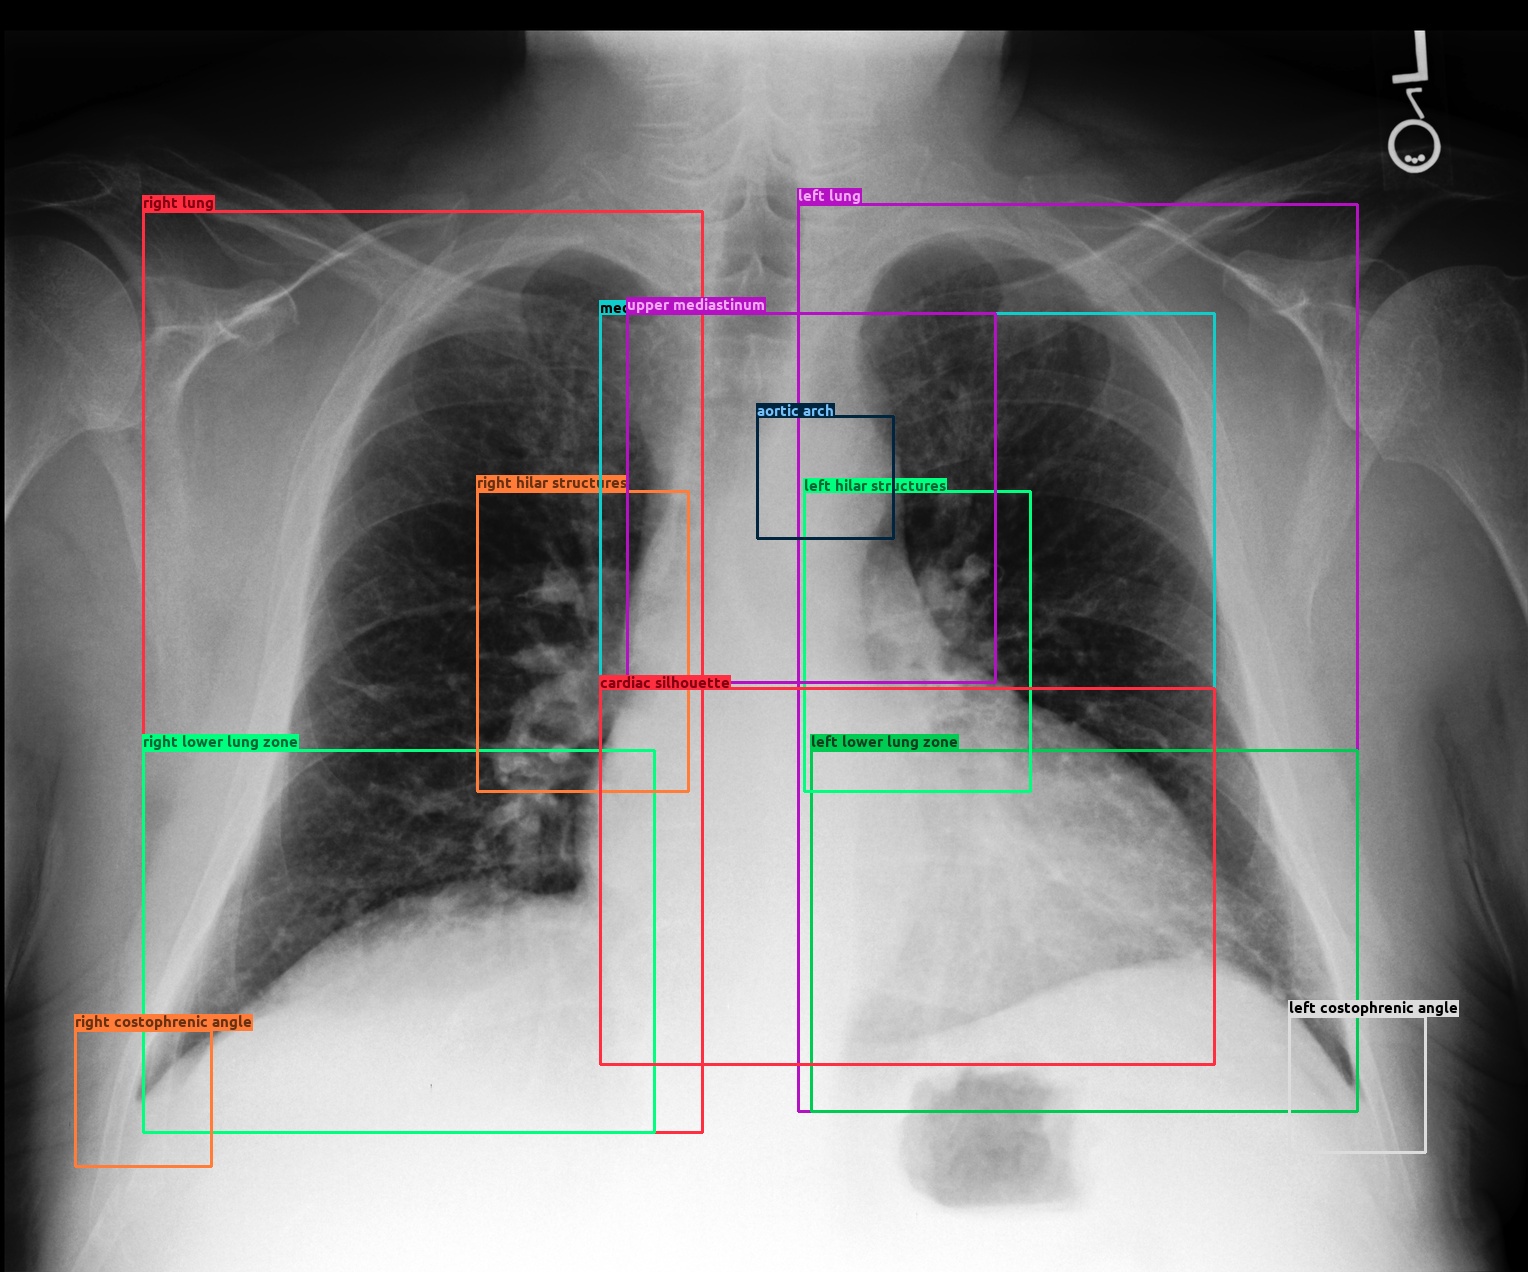

Refer to caption

Figure 2: An image with bounding boxes showing the severe overlapping and noisy annotation problems.

Motivated by this, we propose a novel framework called Scene Graph aided RRG (SGRRG), which leverages the automatically generated scene graph with a transformer model to reveal latent knowledge within each sample, whilst preserving the important original patch-level visual patterns. Specifically, we translate the scene graph via a carefully designed scene graph encoder and introduce a fine-grained token type embedding method to address a severe problem of overlapping anatomical regions in radiology scene graphs, as illustrated in Figure 2. The encoded scene graph, combined with the visual and textual tokens, are then fed into a scene graph-aided decoder with a fine-grained distillation attention mechanism to distill the scene graph knowledge into the model. In addition, SGRGG𝑆𝐺𝑅𝐺𝐺SGRGG integrates key scene-graph generation processes into its generative model, including region-level representation generation, region selection, and attribute prediction. This design renders SGRRG a highly adaptable framework, enabling the easy incorporation of other advanced RRG techniques, such as patch-level representation learning or knowledge enrichment methods. Moreover, we introduce two abnormal information learning modules to facilitate the generation of clinically accurate reports. This work makes four primary contributions:

The final node token set, 𝑺={s1,s2,,sNs}𝑺subscript𝑠1subscript𝑠2subscript𝑠subscript𝑁𝑠\bm{S}=\{s_{1},s_{2},...,s_{N_{s}}\}, comprises both object embeddings and their associated attribute embeddings, where Ns=No+Nasubscript𝑁𝑠subscript𝑁𝑜subscript𝑁𝑎N_{s}=N_{o}+N_{a}. However, as shown in Figure 2, objects in the radiology image are normally highly overlapped. This hinders the encoder’s ability to discern distinct objects and impedes the learning of contextual knowledge. Possible noisy box annotations further exacerbate this problem. To tackle this, we propose applying a fine-grained token-type embedding, namely anatomy embedding. We add to the object embeddings with a learnable token-type embedding for each anatomical category. Equation 11 then becomes 13 where y(oi)𝑦subscript𝑜𝑖y(o_{i}) indexes the anatomical category for the ithsuperscript𝑖𝑡i^{th} object and eoy(oi)subscriptsuperscript𝑒𝑦subscript𝑜𝑖𝑜e^{y({o_{i}})}_{o} denotes the token type embedding for anatomical category y(oi)𝑦subscript𝑜𝑖y(o_{i}).